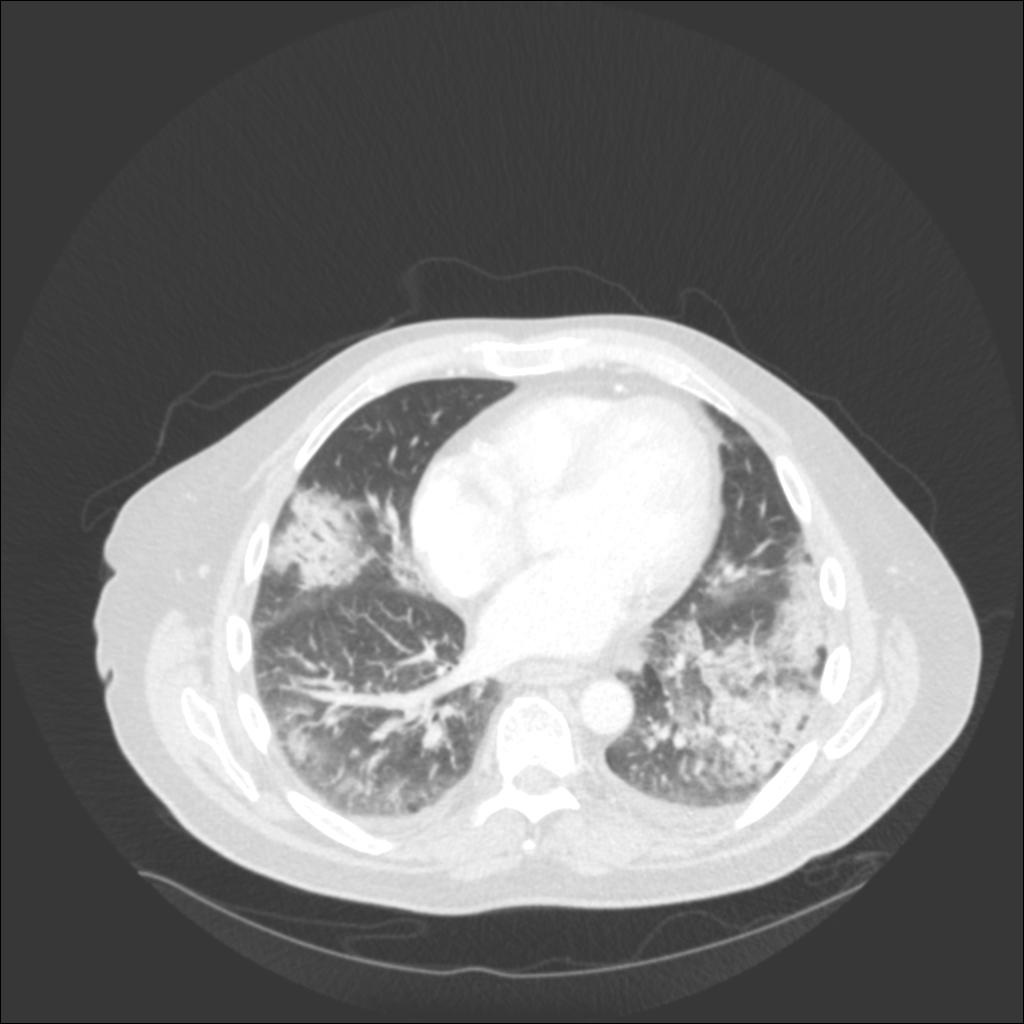

In our patient, the chest radiograph revealed multifocal alveolar infiltrates predominantly in the right upper lobe, left upper lobe, and left lower lobe. Chest CT revealed patchy ground glass and consolidative infiltrates throughout both lungs.